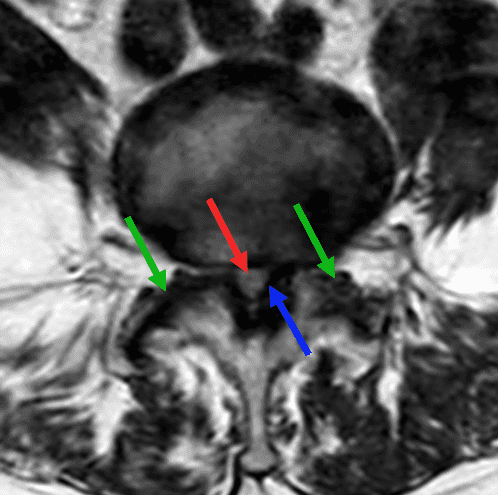

Canal lombaire rétréci

Claudication radiculaire bilatérale d'apparition progressive chez une patiente de 65 ans.